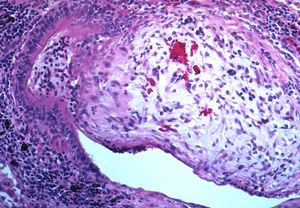

Lung biopsy

Transthoracic lung biopsies are preferable for diagnosis of constrictive BO compared to transbronchial biopsies; regardless of the type of biopsy, a diagnosis may only be achieved by examination of multiple samples.[30] Transthoracic biopsies are preferred over transbronchial due to the heterogeneity and distribution of the lesions.[11] OB can be further classified into two categories: constrictive or proliferative.[11] The constrictive pattern is demonstrated by peribronchiolar cellular infiltrates which eventually causes small airway damage and leads to subepithelial fibrosis.[11] The bronchial muscle can eventually become fibrosed which can be identified with trichrome staining.[11] In regards to proliferative disease, intraluminal buds called "Masson bodies" fill the lumen, which results in bronchiolar plugging.[11] Often people with proliferative disease will show butterfly wing-like appearance under microscopy.[11] One key determinate that can be seen on biopsy to differentiate constrictive from proliferative disease is the extent of lesions. Both lesions are localized from the small bronchi to the membranous bronchi, but in constrictive disease the lesions are intermittent while proliferative disease has a continuous distribution.[11]